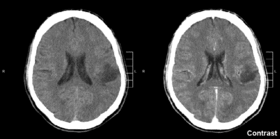

![]() ورم دبقي في الفص الجداري الأيسر. صورة بالأشعة المقطعية للدماغ. | |